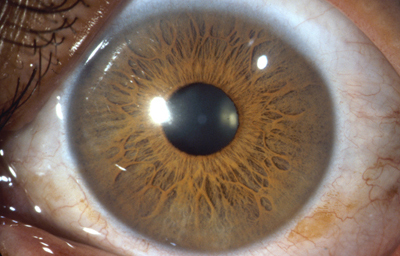

Foto de un Iris humano adulto, con residuos avasculares pigmentados de la membrana pupilar, viniendo del circulo menor. No tiene criptas.

Tomada del archivo fotografico del Dr. CB

Alrededor del 7º mes la vascularización de la porción mesodérmica del Iris, (estroma iridiano) está llegando a su condición definitiva y el circulo vascular menor se reconoce; la túnica vasculosa lentis ya se ha atrofiado en sus porciones posterior y lateral, e inicia atrofia de su porción anterior (membrana pupilar) afectando en primer lugar su zona central; primero en las arcadas finales del centro los vasos se encogen, pierden circulación y quedan formando pequeñas espirales; el ectodermo iridiano con el esfínter ya se ha profundizado, está a nivel de las segundas arcadas vasculares de la membrana pupilar; cuando progresivamente la segunda arcada se atrofia, la membrana queda separada del margen pupilar y toma la apariencia de 2 capas: una anterior (la membrana pupilar) y otra posterior, el margen de la verdadera pupila. Esa grieta o seudoespacio tiene una extensión muy variable; por lo general, solo se ve en el borde de la pupila, pero puede ocurrir que comprometa la capa superficial de vasos periféricamente. Puede ocurrir que el proceso de atrofia no se detenga en la infancia y continue lentamente a lo largo de la vida, hasta que al final toda la hoja vascular anterior se separe del estroma profundo y quede flotando libre en la cámara anterior unida únicamente en la máxima periferia al estroma iridiano (Iridosquisis).

Lo que generalmente se ve, son parches de atrofia localizados periféricamente al margen pupilar, que toman la apariencia de criptas en el estroma.

El modelado final del Iris adulto, tendrá gran cantidad de variaciones dependientes de la cantidad de atrofia de su hoja anterior y de la pigmentación que desarrolle.

El desarrollo del pigmento en el Iris ocurre después del nacimiento y se define después de los 6 meses. Es de anotar que el esculpido del Iris que se aprecia en los adultos con ojos azules o grises, es debido a la visibilidad de las paredes de los vasos; en los iris muy pigmentados el detalle de la estructura queda oculto.